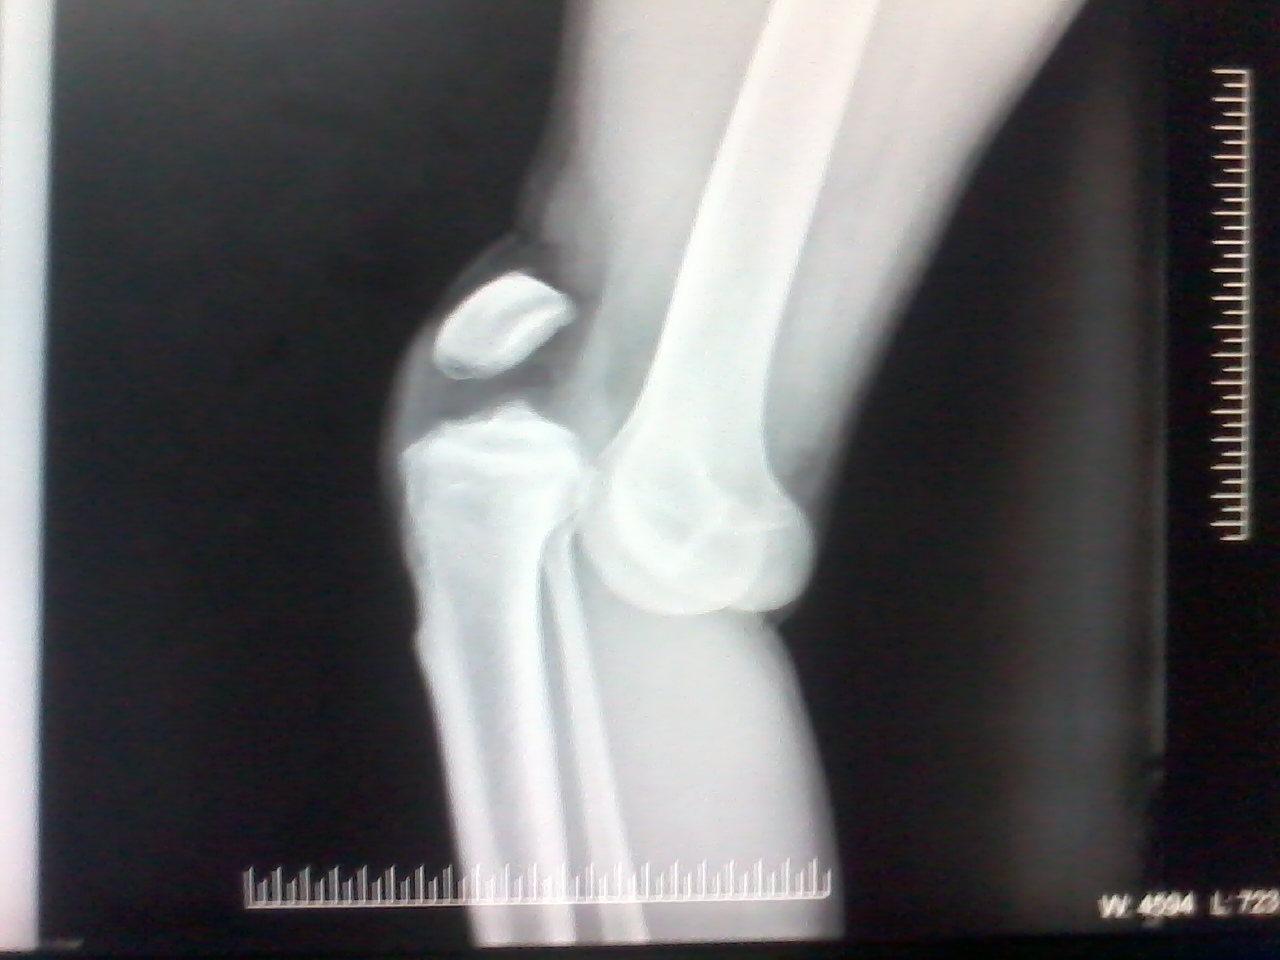

Doctors commonly use imaging scans such as X-ray, MRI, and CT scans to produce an image of your bones and cartilage. This helps them rule out other causes of your symptoms, such as bone spurs.

X-rays. Because a torn meniscus is made of cartilage, it won’t show up on X-rays. But X-rays can help rule out other problems with the knee that cause similar symptoms.

MRI. This uses a strong magnetic field to produce detailed images of both hard and soft tissues within your knee. It’s the best imaging study to detect a torn meniscus.